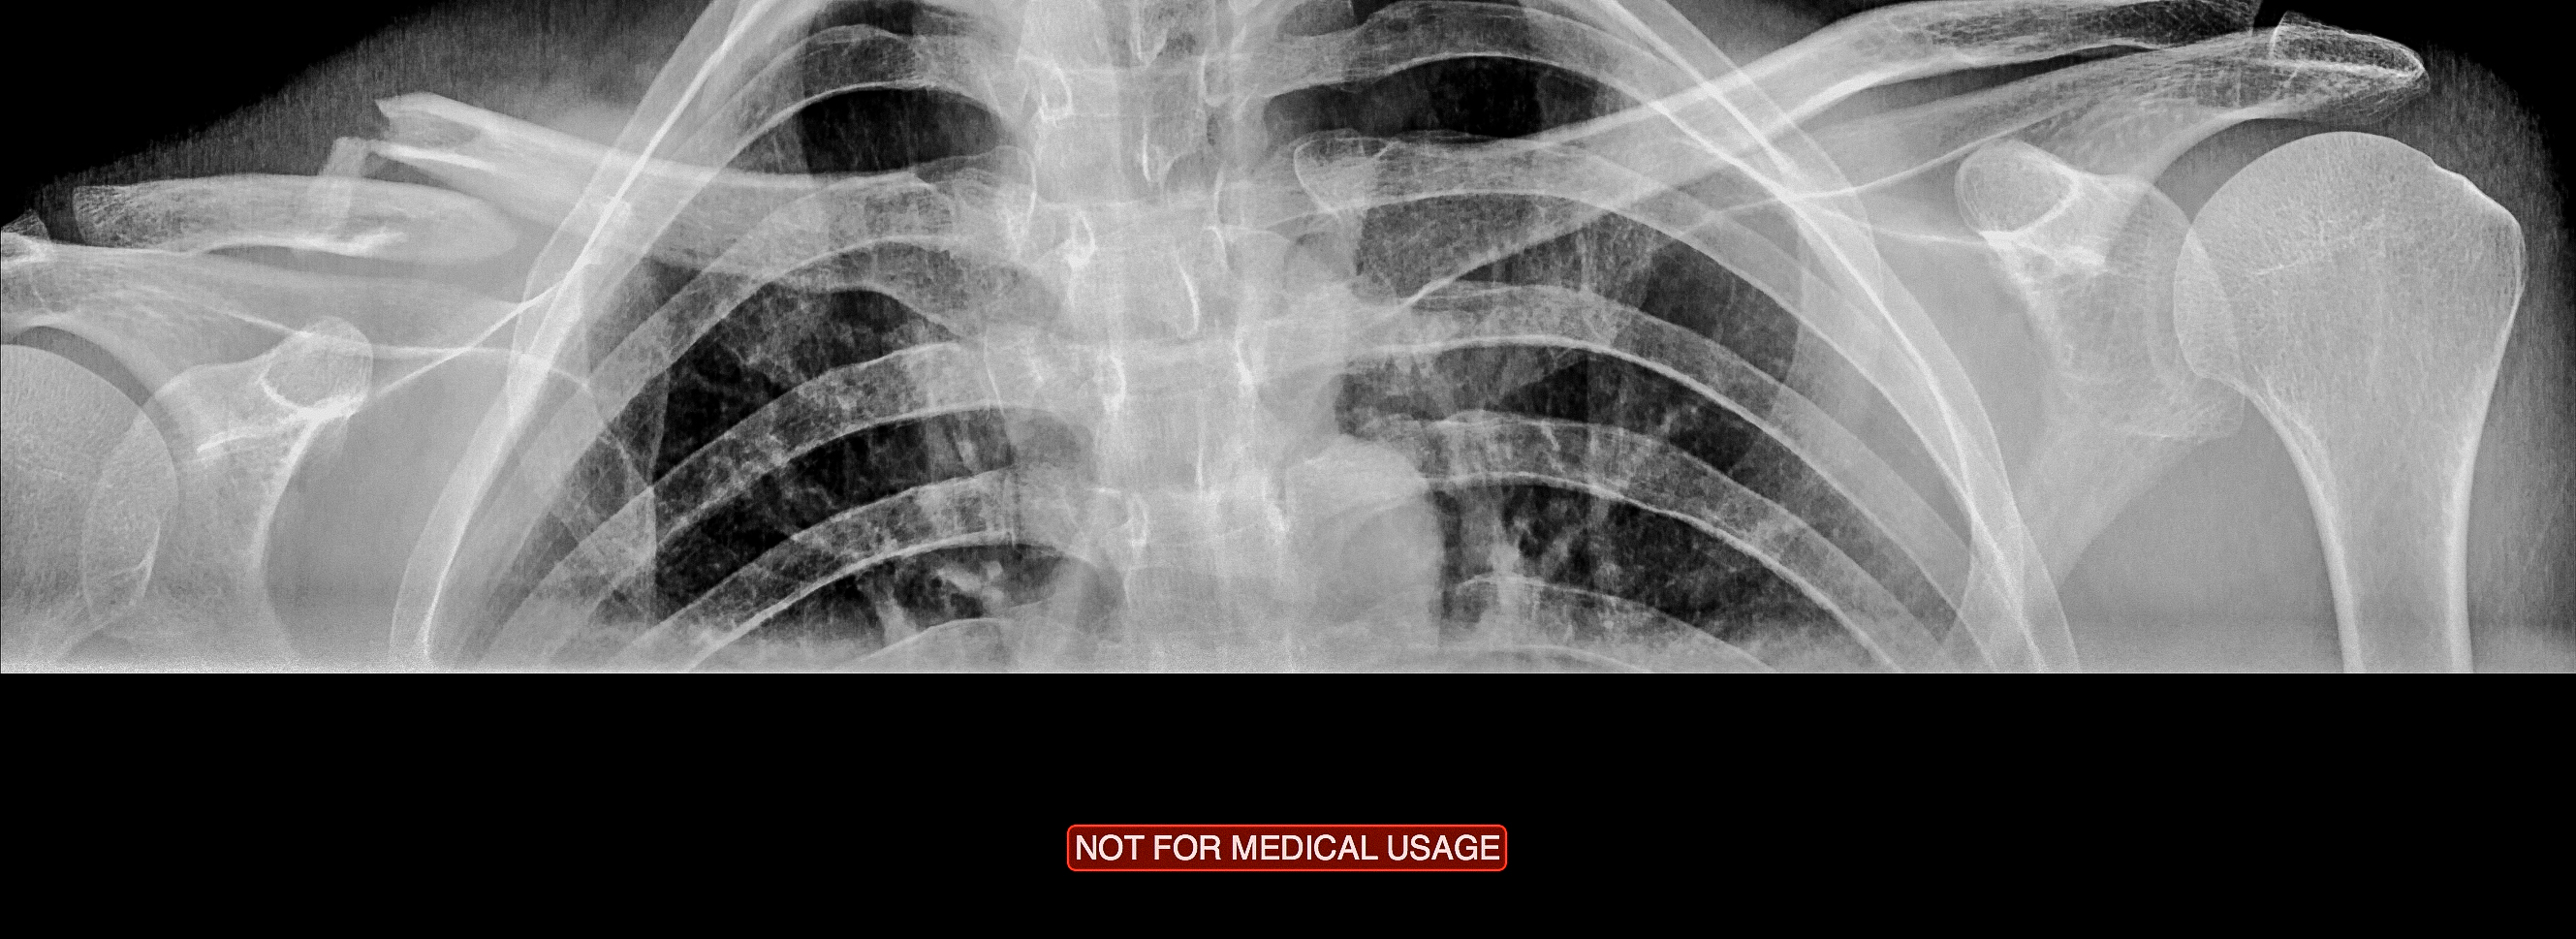

Akutten på Lillehammer Sykehus vil ikke ta meg imot, og jeg blir i stedet henvist til Kirurgisk Poliklinikk. Den middelaldrende damen i skranken rister bare oppgitt på hodet når jeg forteller at dette var en sykkelulykke, midtvinters. Køen er heldigvis til å leve med, og jeg får raskt tilsyn av en ung turnuslege. Det stilles spørsmål, klemmes, bøyes, tøyes og fotograferes i en tiltagende døs av smertestillende. En salig blanding av Tramadol, Paracetamol, medbrakt Clif Bar og sur sykehuskaffe gjør jobben.

Min umiddelbare mistanke blir raskt bekreftet: Kragebeinsbruddet er et faktum!